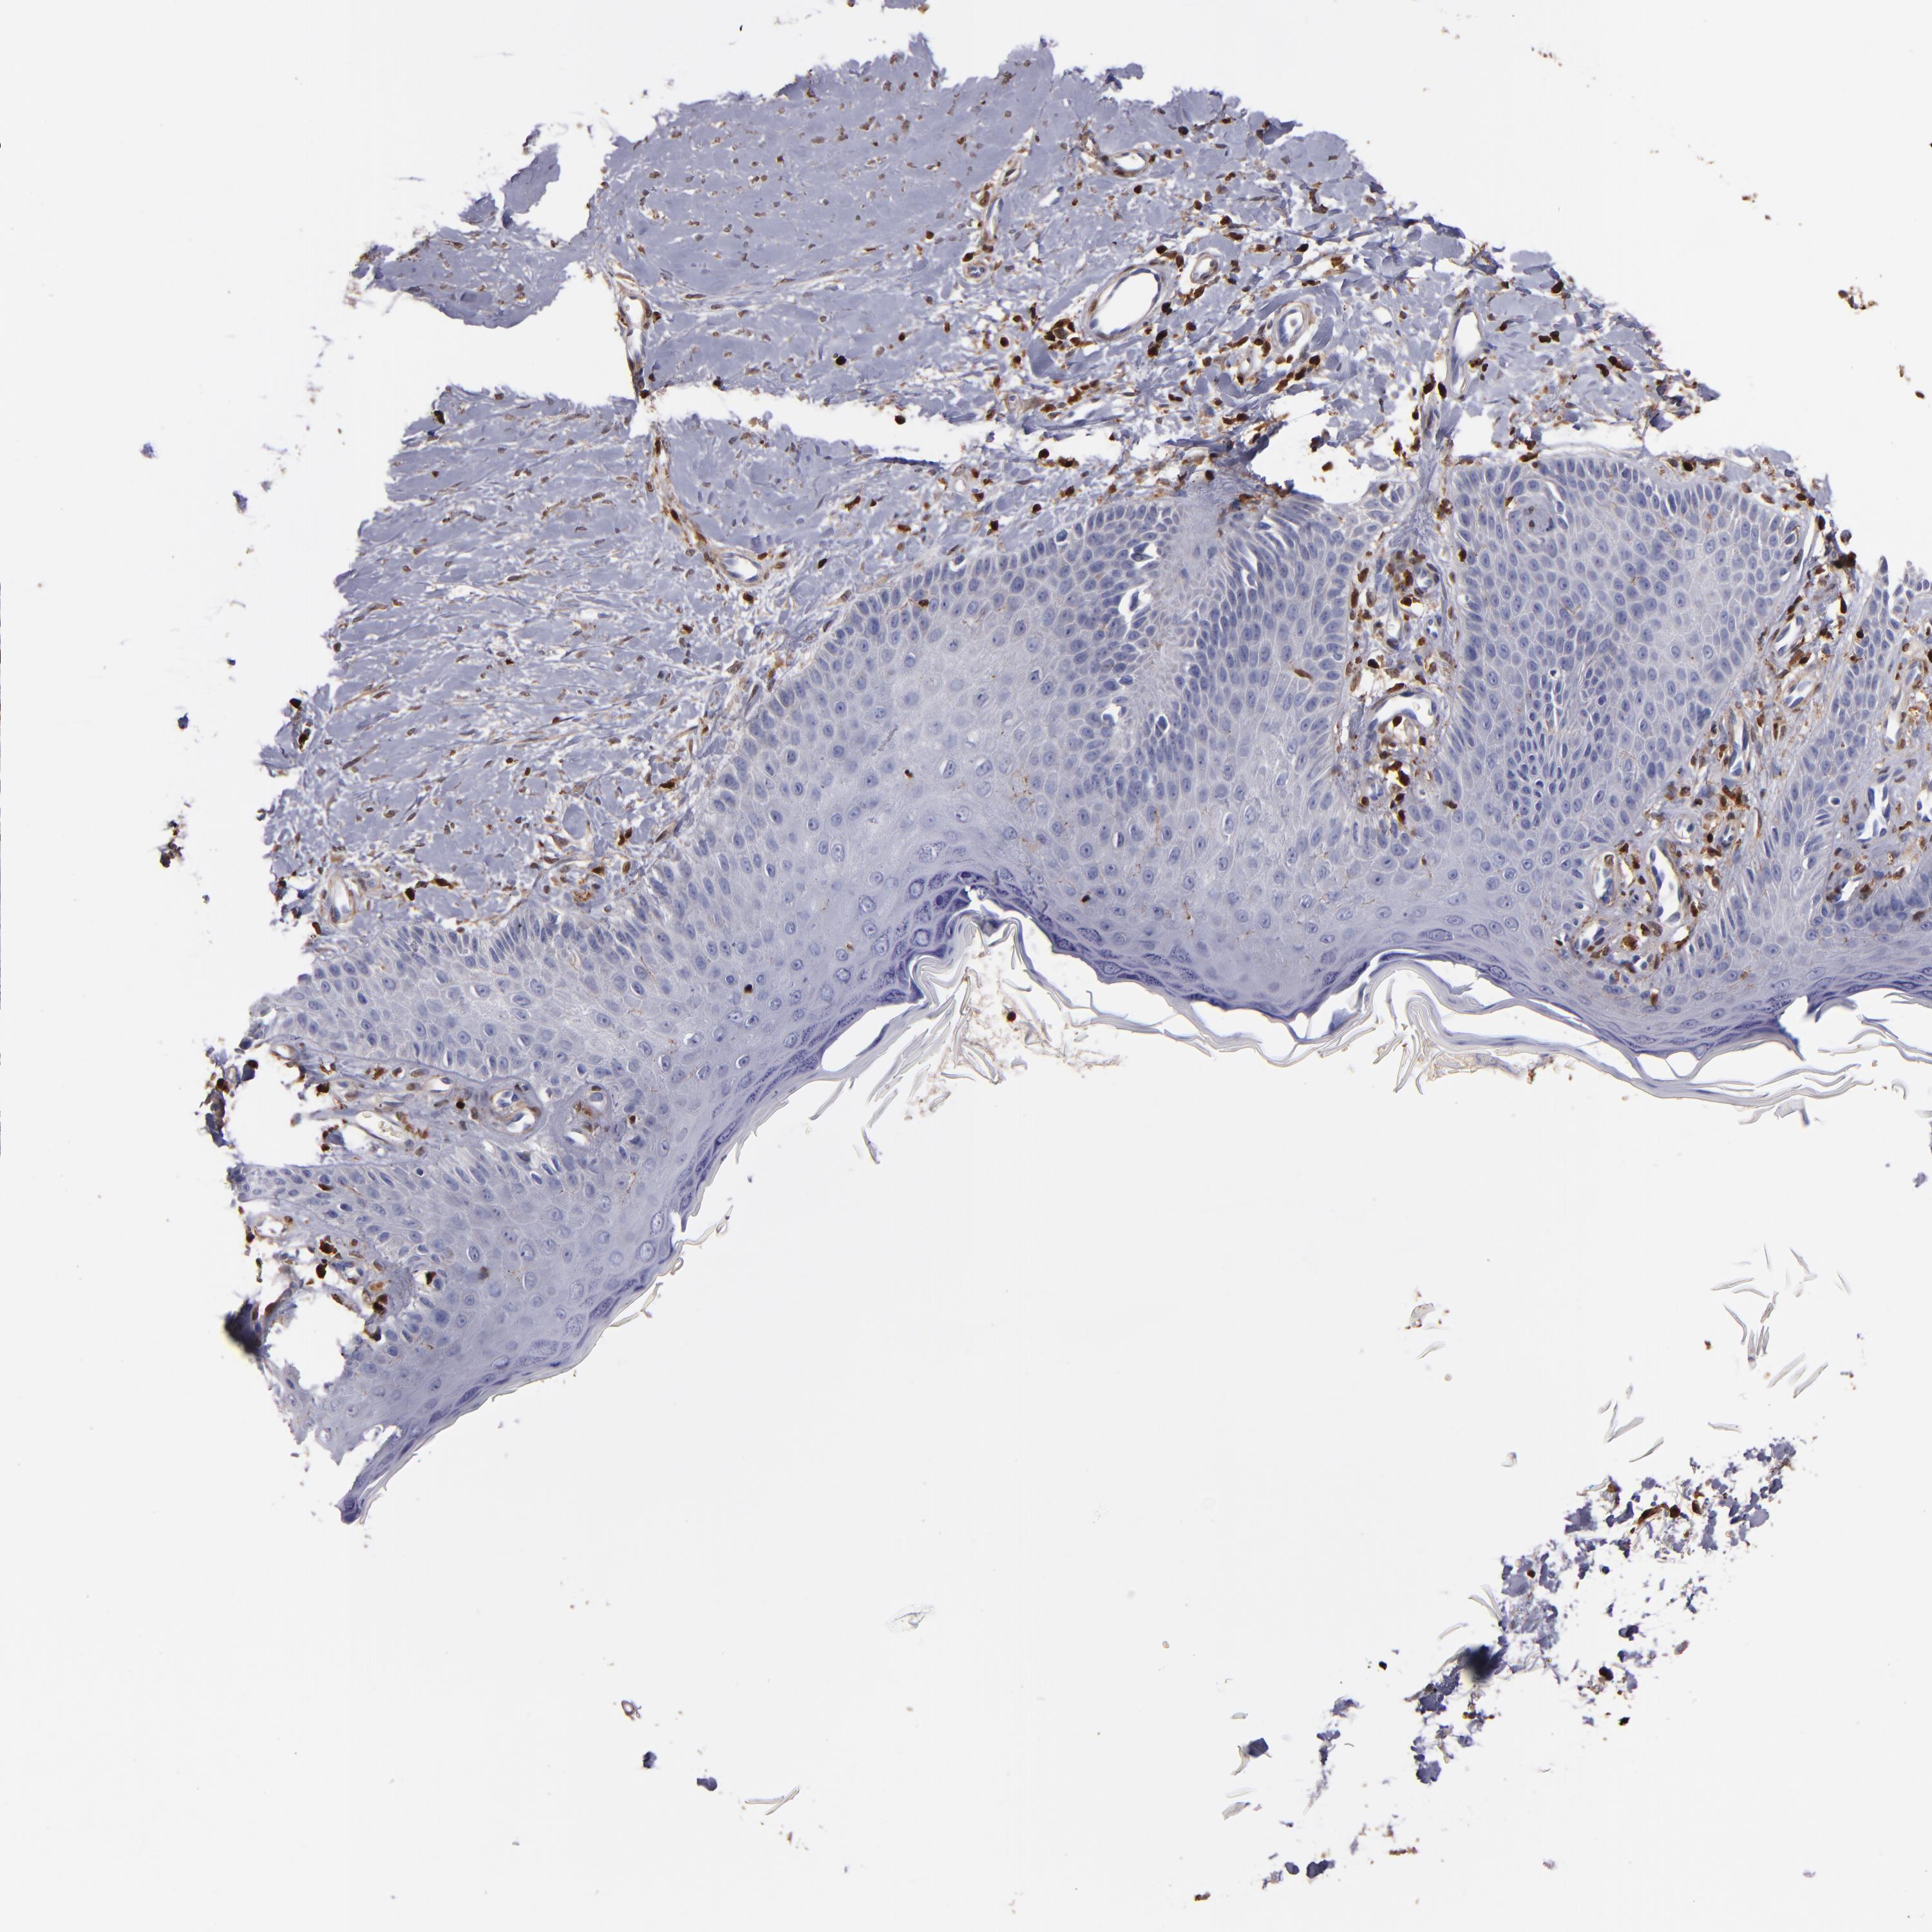

CANCER SKIN CANCER Show tissue menu

Basal cell and squamous cell cancer

SKIN CANCER - Protein expressioni

A mouse-over function shows sample information and annotation data. Click on an image to view it in a full screen mode. Samples can be filtered based on level of antibody staining by selecting one or several of the following categories: high, medium, low and not detected. The assay and annotation is described here.

Each image is clickable and will lead to virtual microscopy that enables deeper exploration of all samples and also displays staining intensity scores, fraction scores and subcellular localization as well as patient and tissue information for each sample.

CAB002618

Squamous cell carcinoma, NOS